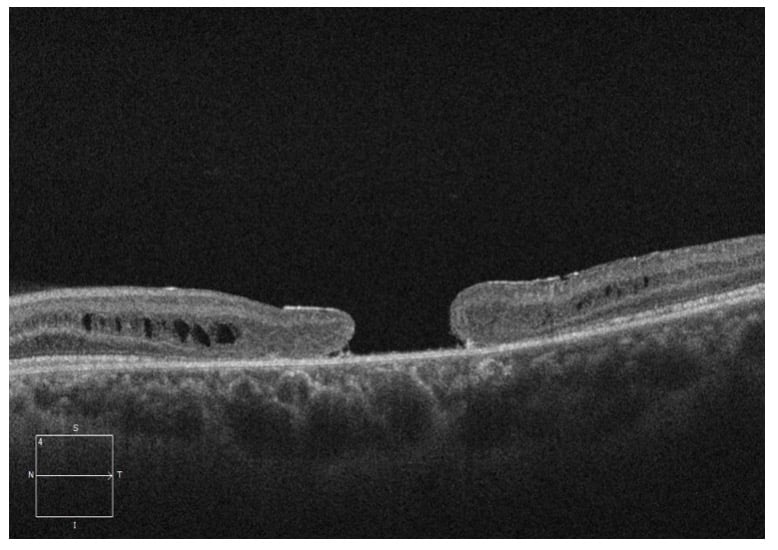

A 25-year-old male was referred for a second opinion of progressively worsening vision OU for the past 14 years. His ocular history was significant for previous diagnosis of macular hole OU as a child. The Fundus exam revealed bilateral large macular holes with yellow/brown pigmentation OU (figure 1). OCT (Optical Coherence Tomography) confirmed the full thickness macular holes with foveal retinoschisis OU (figure 2). Given the history of pediatric bilateral macular holes in absence of trauma, Electroretinogram (ERG) was performed, which showed decreased B-waves (negative ERG) in both eyes (figure 3), consistent with X-linked retinoschisis.